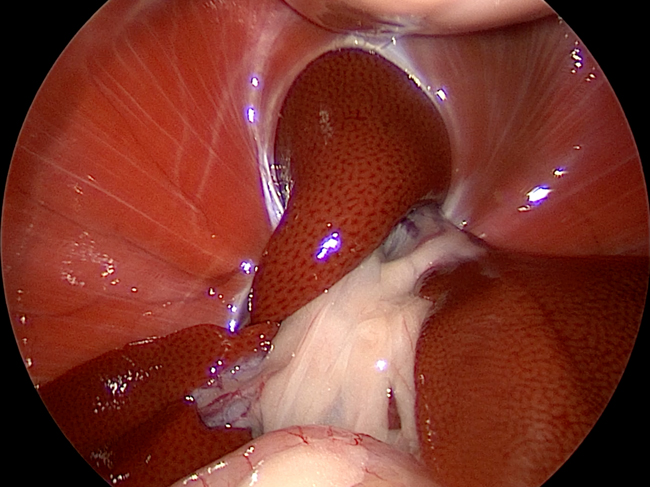

手術の様子

左:腹腔鏡下での逸脱臓器の確認

右:逸脱した臓器を戻した様子